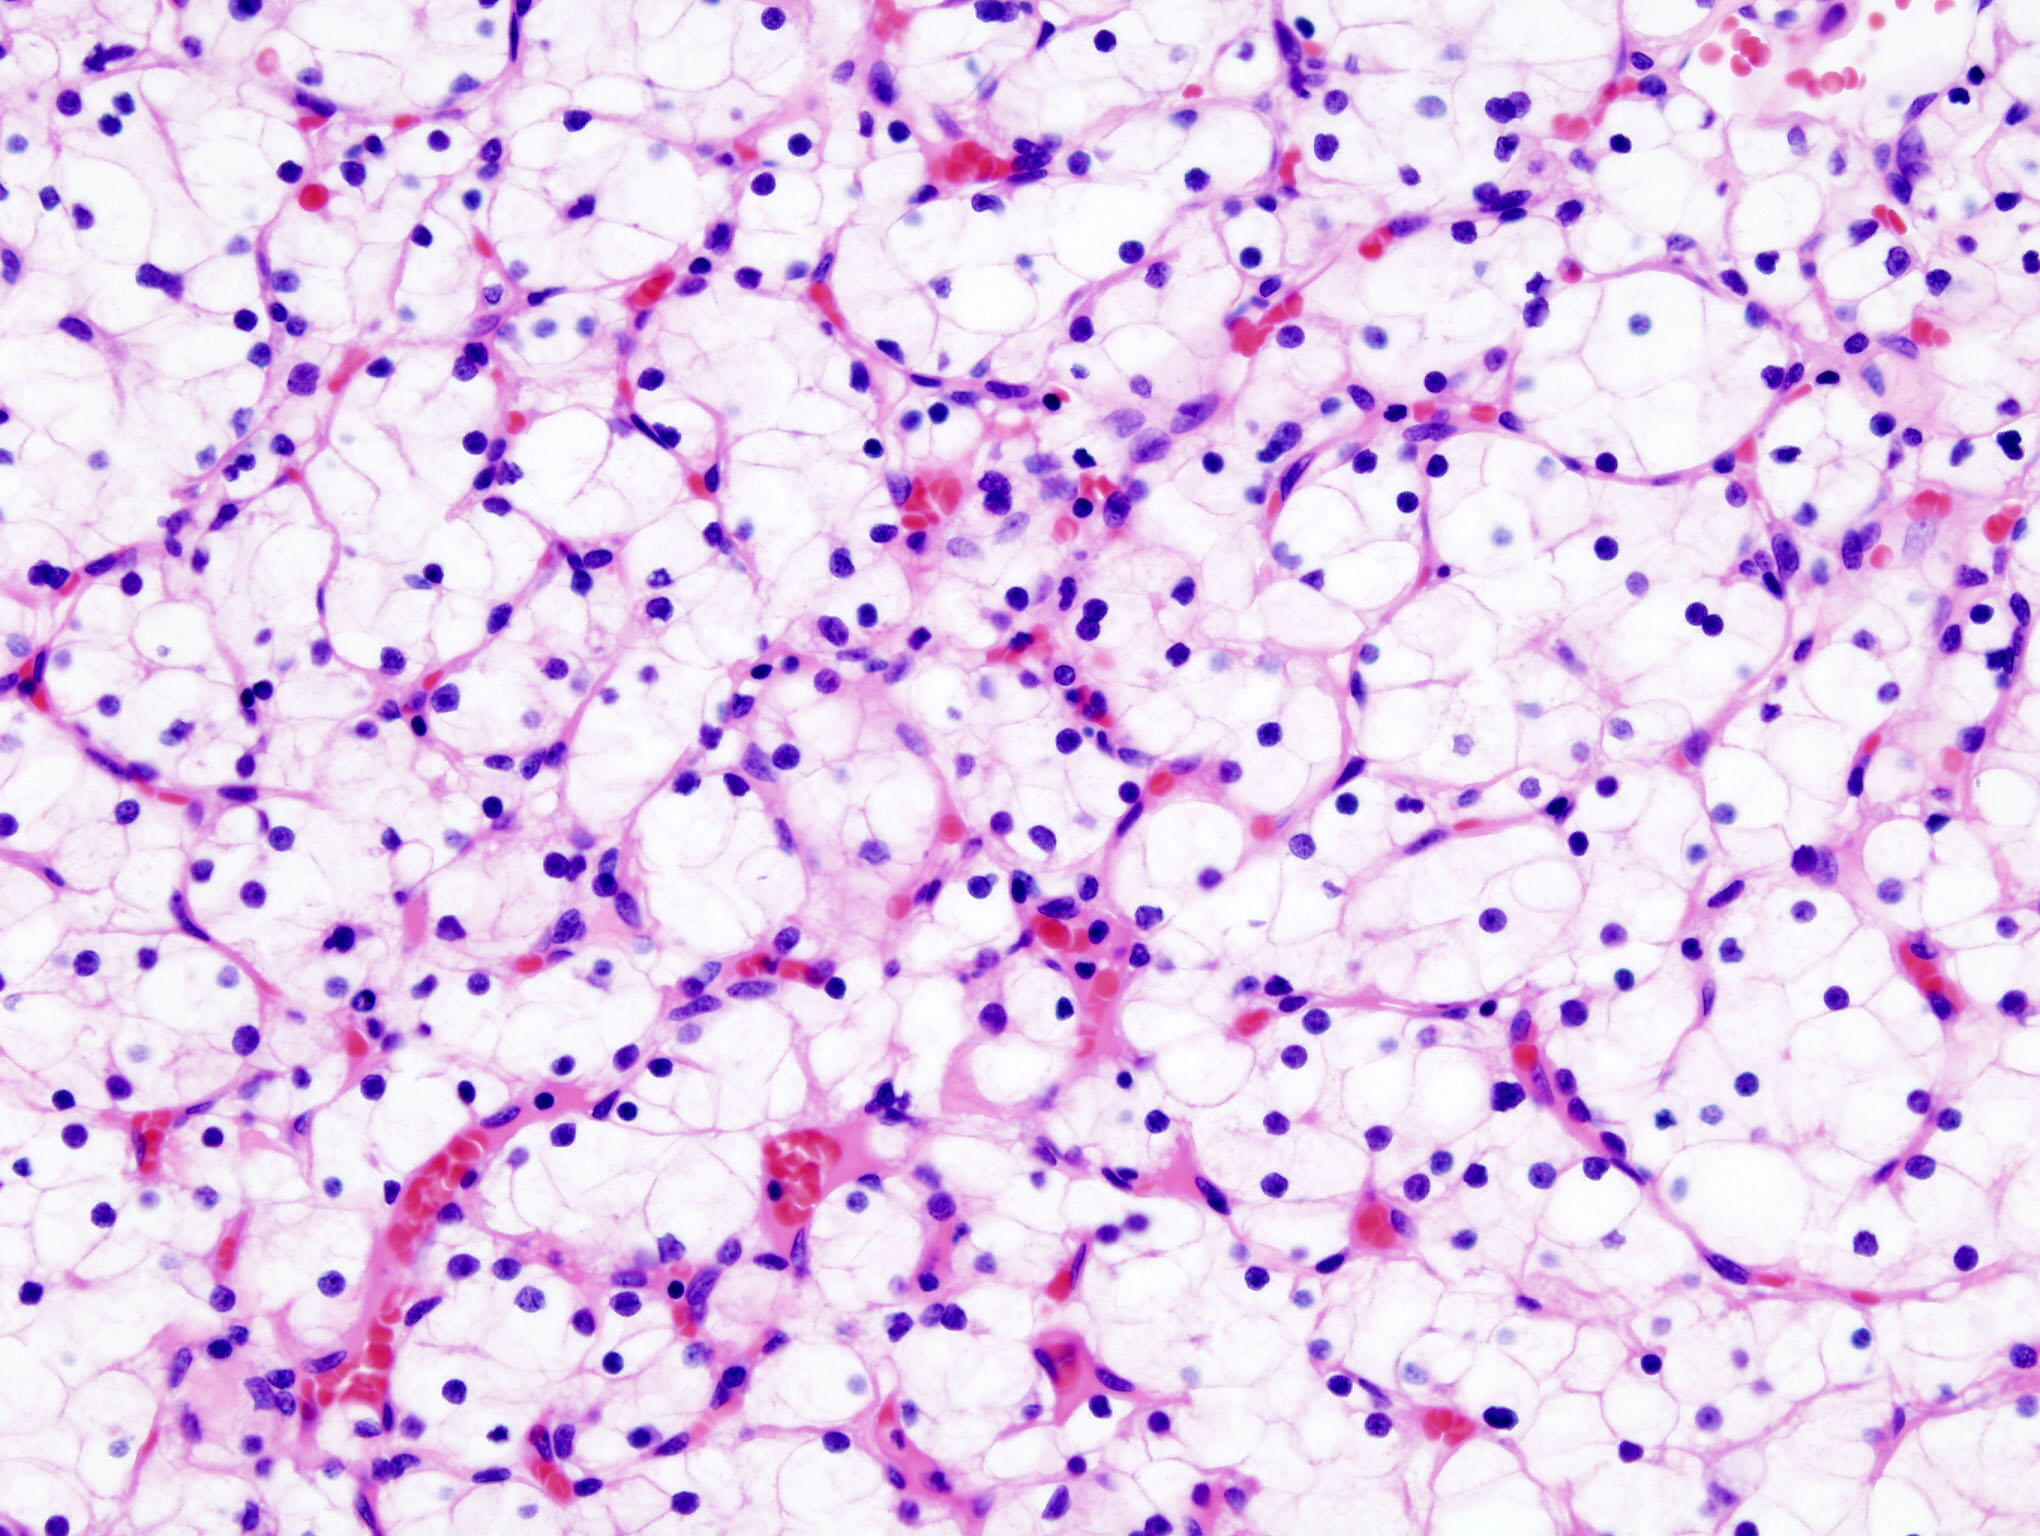

Beim klarzelligen Nierenkarzinom fanden Forscher vom DKTK Essen eine stumme Mutation mit großer Auswirkung auf die Prognose. © Wikipedia